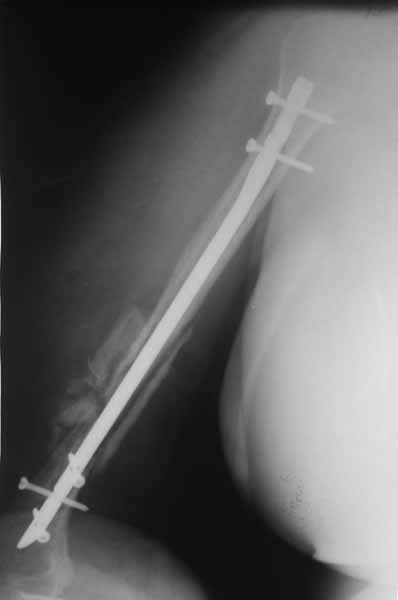

Плечевой сустав на сегодняший день спустя 10 мес. после травмы.